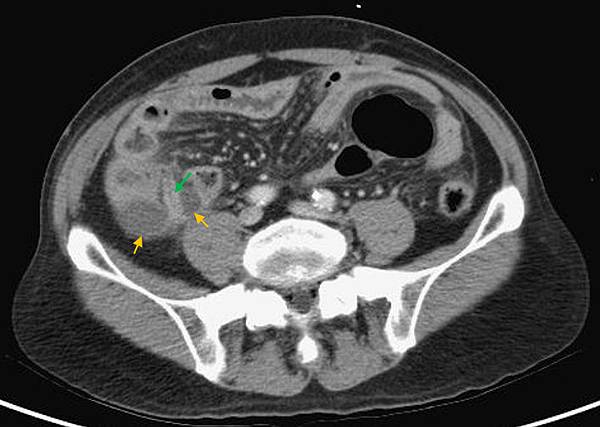

是胃/十二指腸或小腸或大腸破了!一個胃或腸的小破洞,電腦斷層無法判定哪兒破了,一般外科開下去發現是遠端降結腸(Distal descending colon)破了一個洞(0.5 cm),於是找直腸外科繼續完成手術。